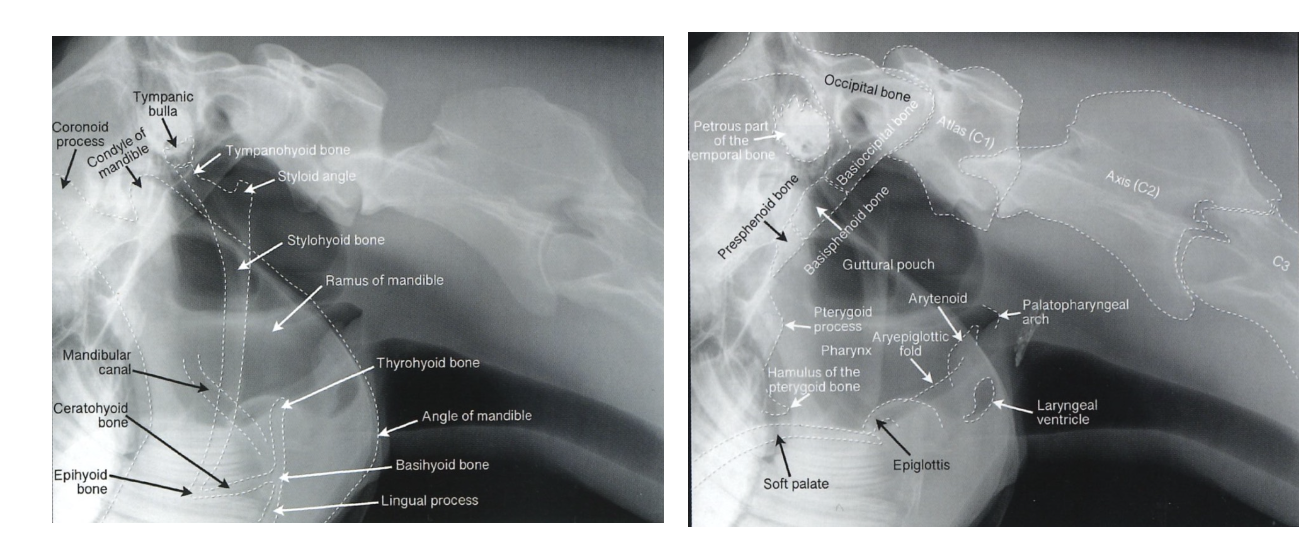

What is latero lateral view used for?

Good for assessing the paranasal sinuses, guttural pouches & pharynx

but cheek teeth superimposed on each other

Latero-lateral view anatomy for reference